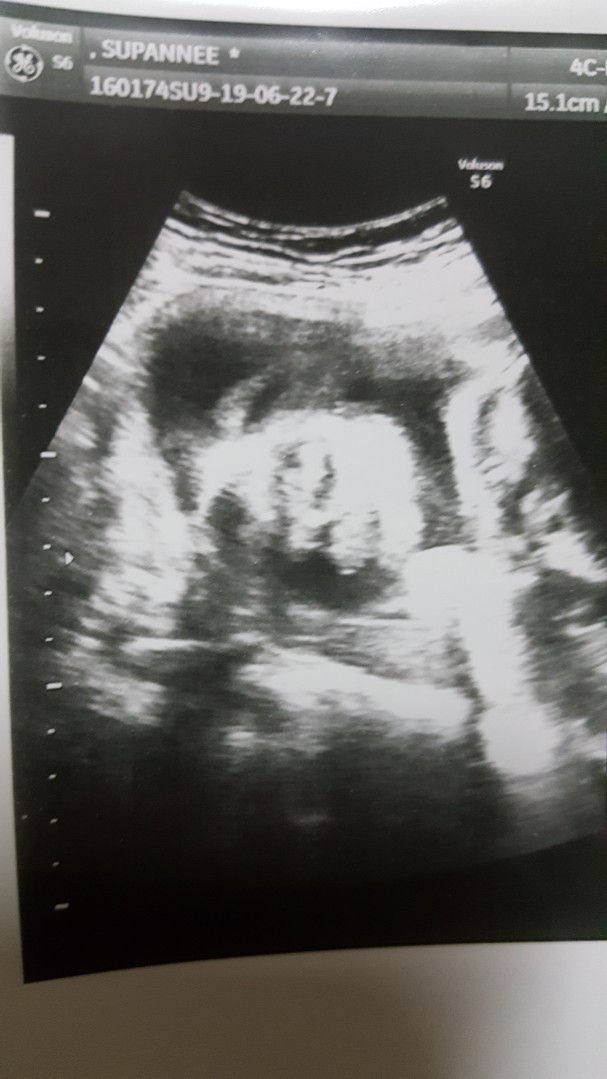

ของเรา 22 วีคค่ะ

ตอน13+2w ตอนนี้ 22+1 แล้วจ้า